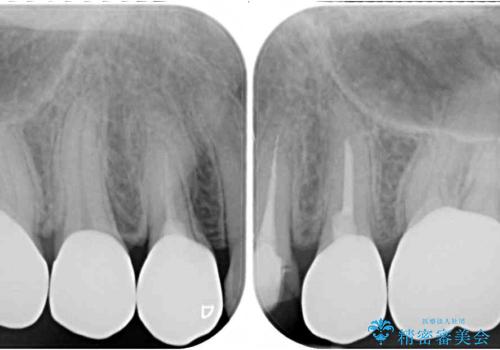

億劫に感じて治療を先延ばししていたそうですが、始めてみるとスムーズに治療が終わり、早く始めておけば良かったと仰っていました。

他にも加療の必要な歯があるので、定期健診を行いながら再開していく予定です。